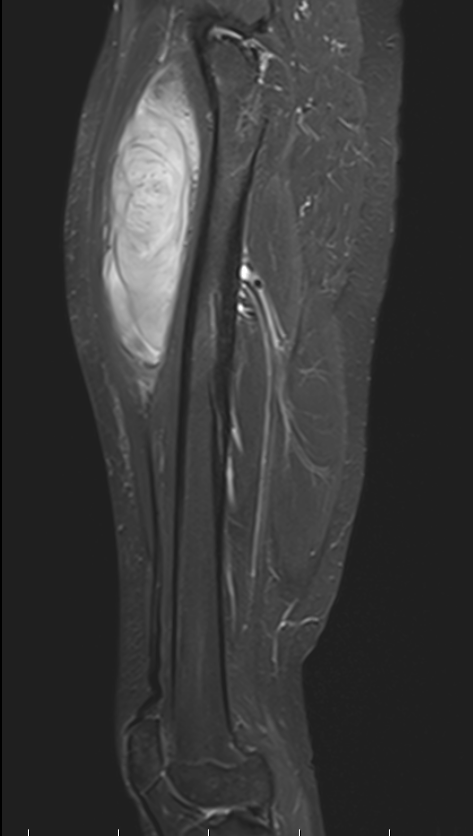

MRI

Superficial tibial sarcoma